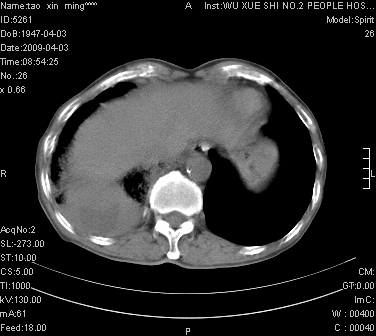

男.62.咯血.胸痛

是不是外伤的,看起来右侧肋骨骨折,右肺唑伤,右胸腔积血, 右肺背段可见一软组织肿块,边缘清晰,可以和中中央型肺ca合并

肺出血,周围型肺癌,右侧胸腔积液

右下周围型肺癌,右侧胸腔积。

右下周围型肺癌,右下肺出血,右侧胸腔积。

1)考虑右肺下叶周围型肺癌,并右肺下叶肺出血。2)右侧少量胸腔积液。

1)考虑右肺下叶周围型肺癌。2)右侧少量胸腔积液。

右下肺阴影,右胸腔少量积液。